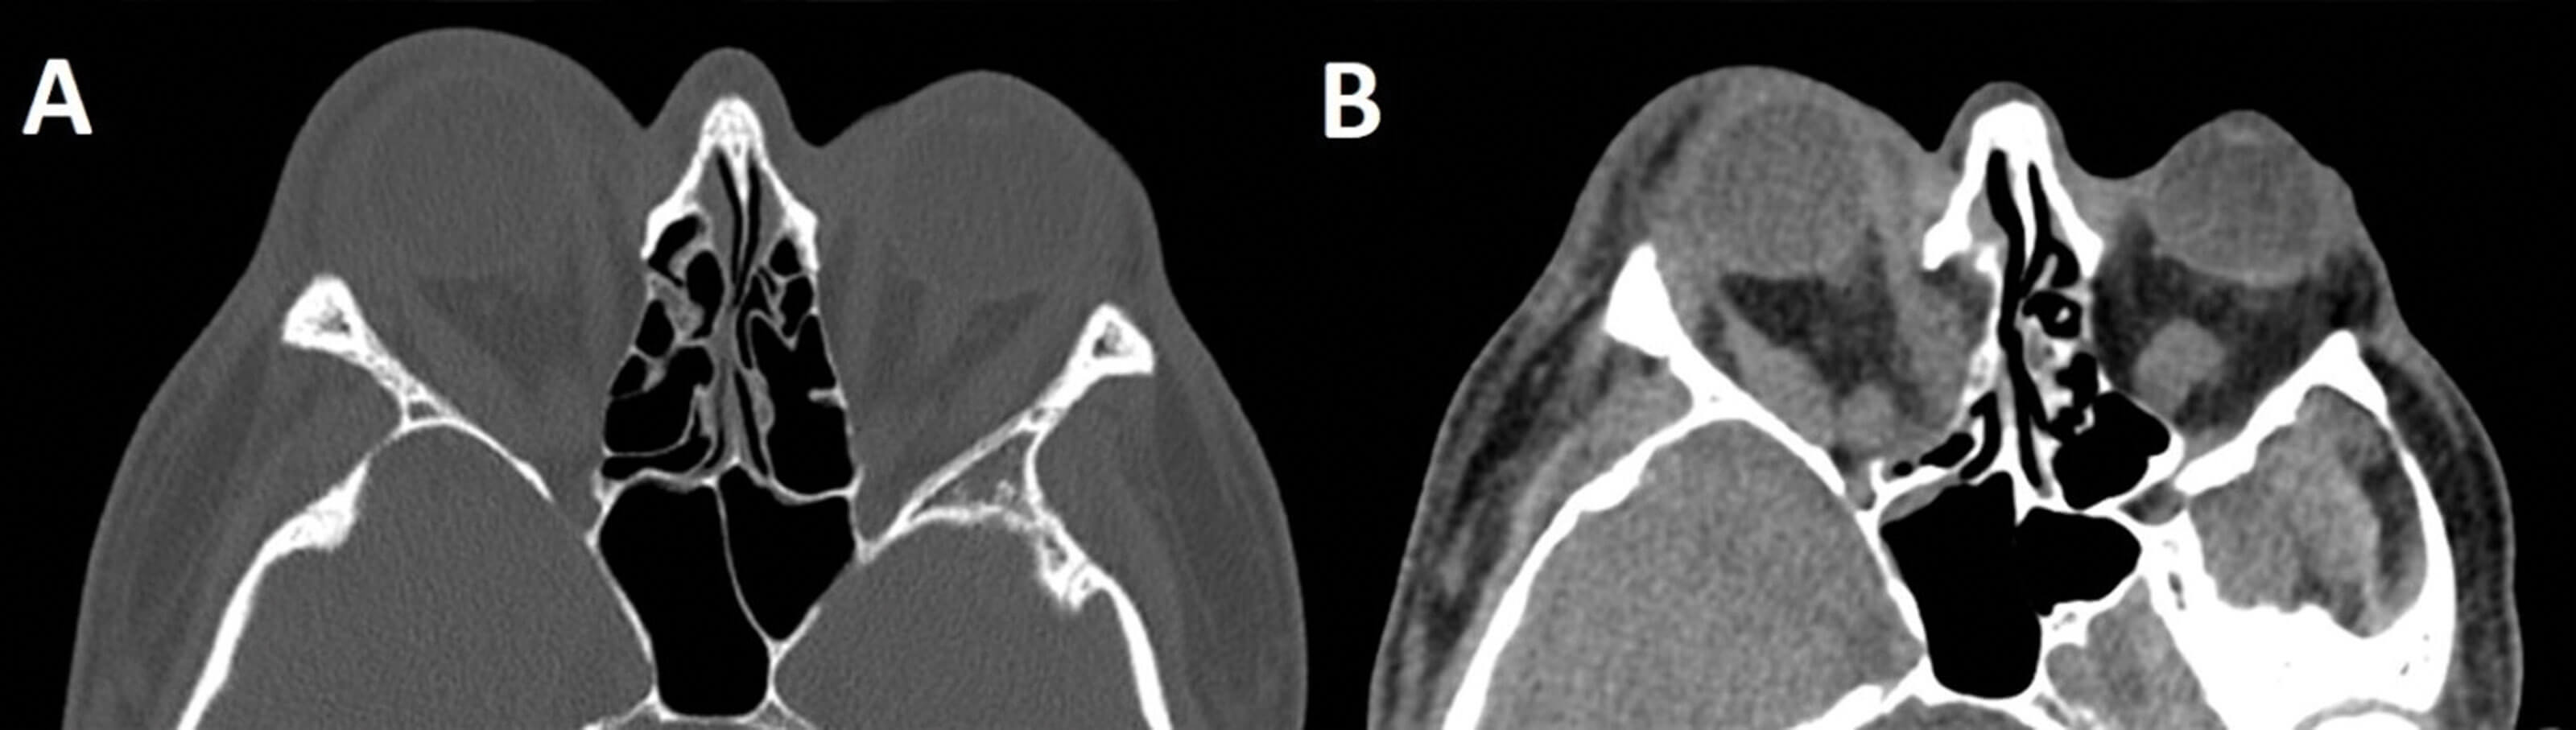

Figure 3. Pre and postop CT images of a patient with severe Grave’s ophthalmopathy. The postoperative CT neck performed prior to thyroidectomy demonstrates the right sided ‘two wall’ decompression and resulting prolapse of periorbital fat into the nasal cavity. A = preop axial slice showing severe exophthalmos with the entire globe anterior to the orbital rim. B = postop axial slice showing prolapse of orbital contents into nasal cavity and reduction in exophthalmos.